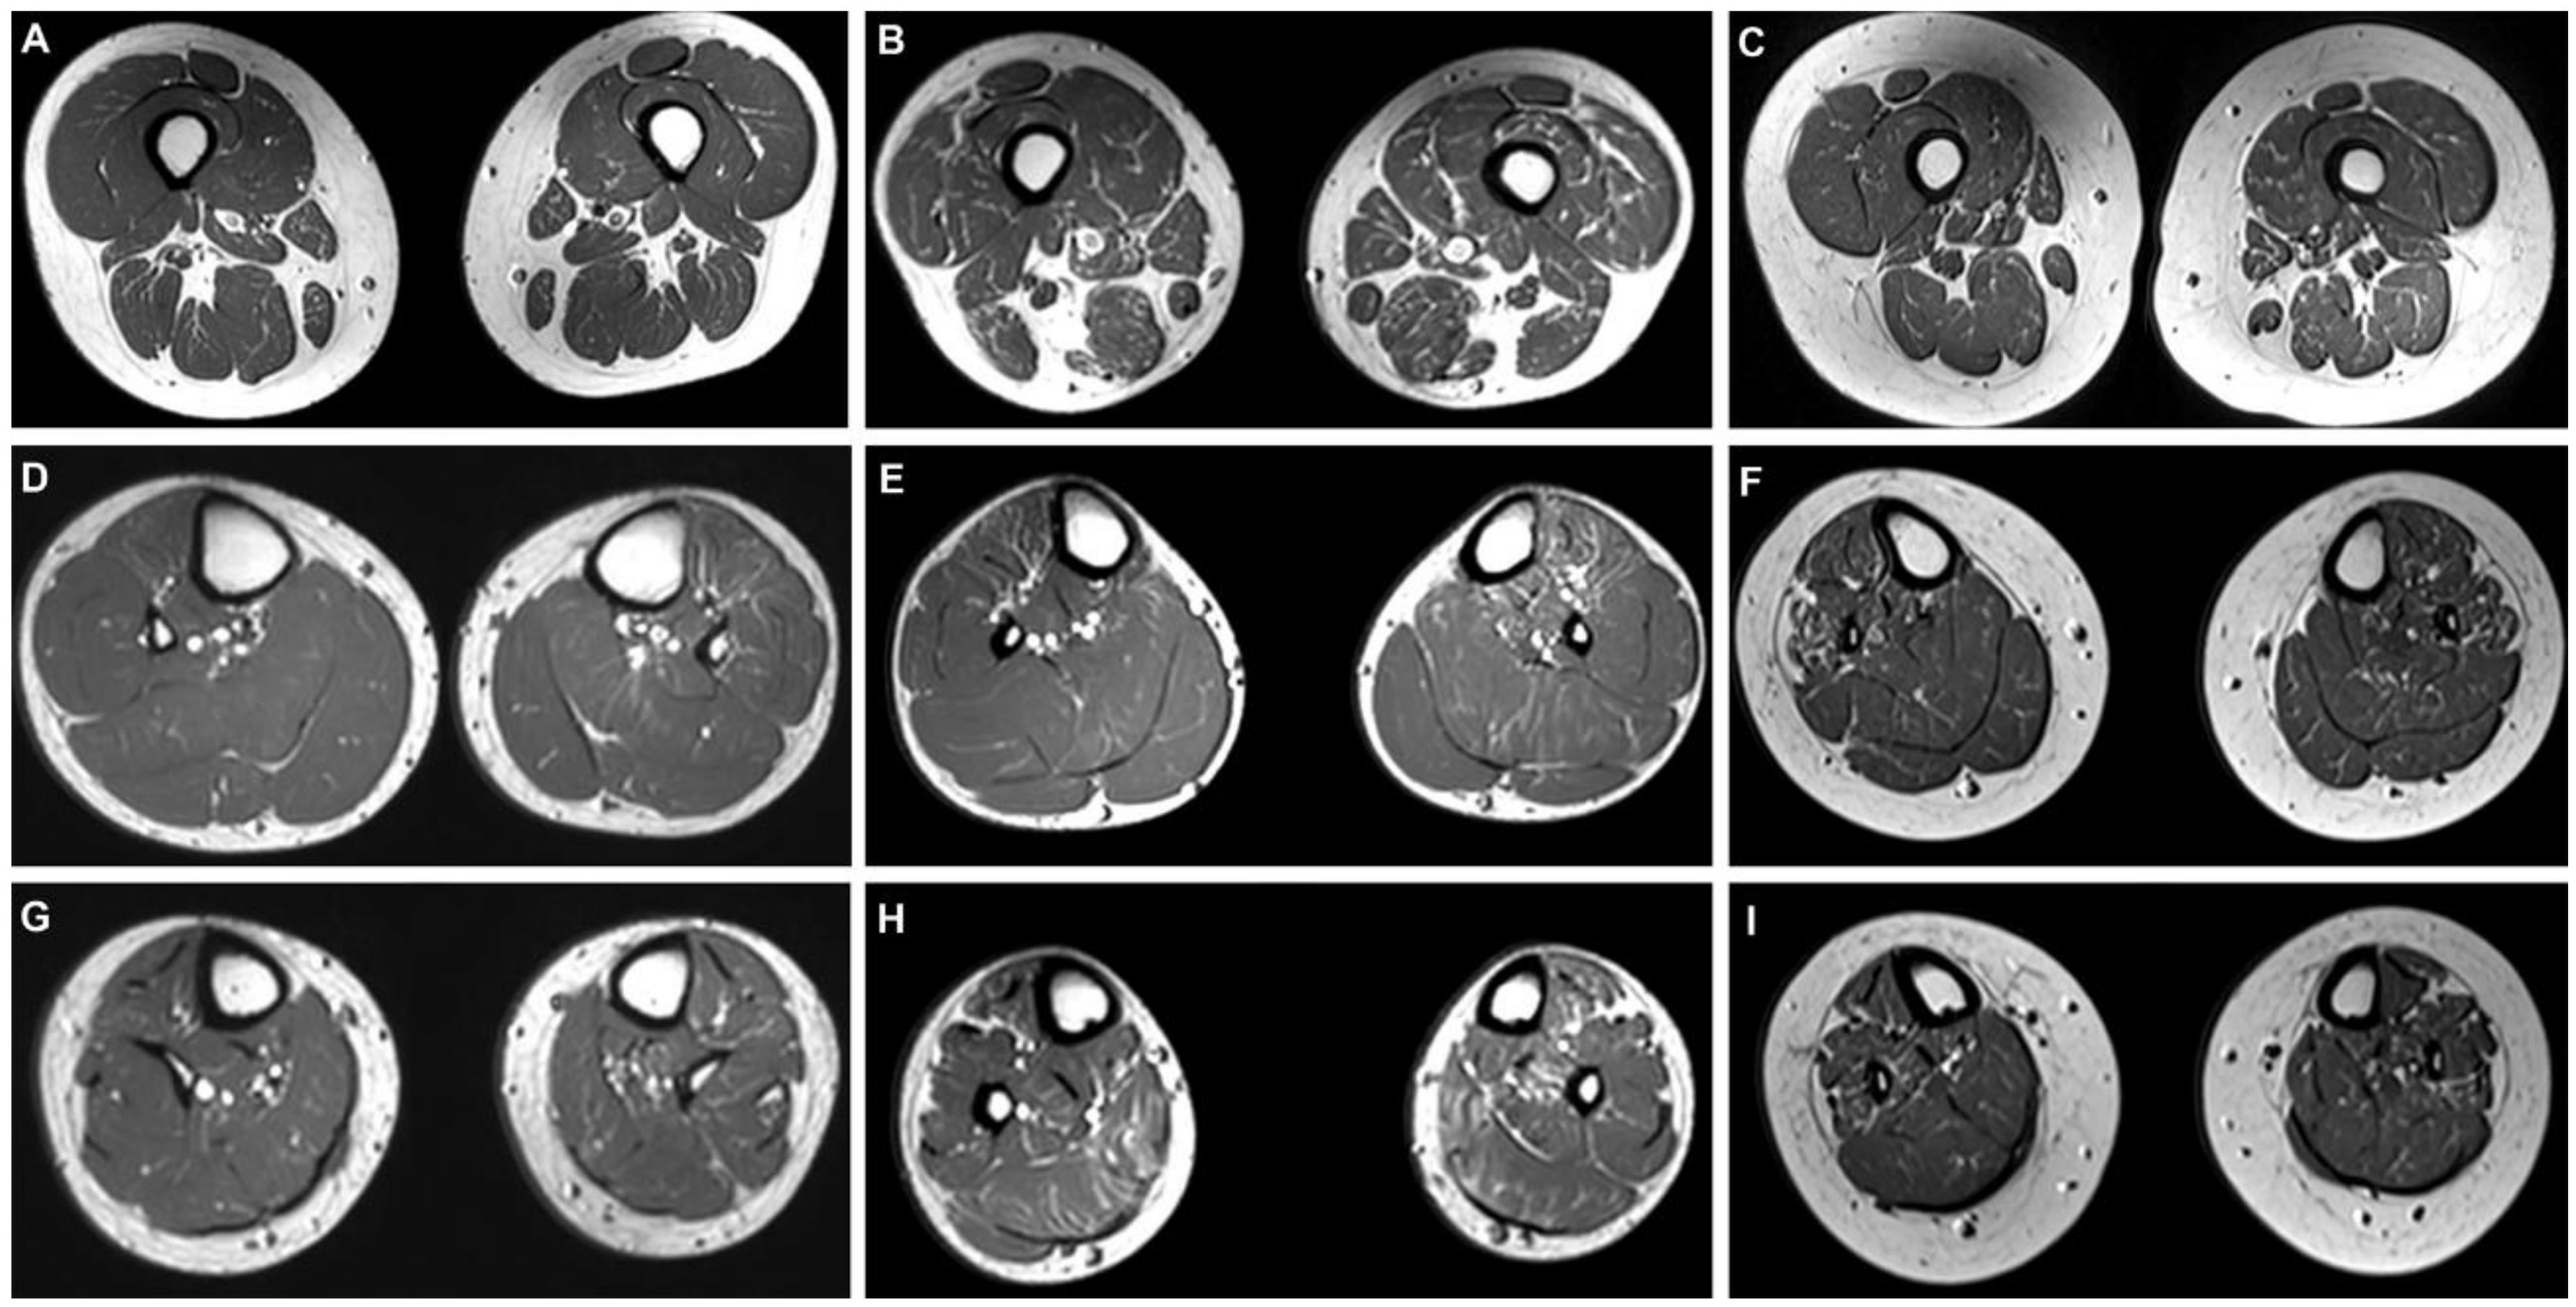

3.5. Lower Limb MRI Features